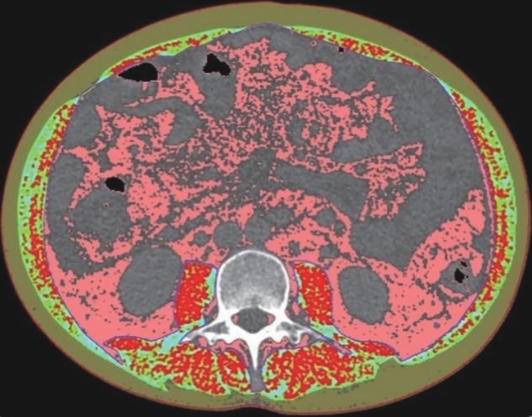

Value of internal stratification analysis of abdominal wall muscles in predicting complications after orthotopic liver transplantation

Xin SHI, Chongxiao LIANG, Bei ZHANG, Jiping WANG

2025, 41(2): 314-321. DOI: 10.12449/JCH250218

Abstract(738) HTML (351) PDF (3265KB)(53)

Abstract:

Objective  To divide the muscle into different subzones according to different density ranges using the stratified analysis on the basis of myosteatosis, and to investigate the effect of muscle density changes on complications (Clavien-Dindo grade ≥Ⅲ) after orthotopic liver transplantation (OLT).  Methods  A retrospective analysis was performed for the medical records of 145 patients who underwent OLT in The First Hospital of Jilin University from May 2013 to September 2020, and with the plain CT scan images of the largest level of lumbar 3 vertebrae of each patient as the original data, Neusoft Fatanalysis software was used to measure related muscle parameters. The independent-samples t test was used for comparison of normally distributed continuous data between two groups, and the Mann-Whitney U test was used for comparison of non-normally distributed continuous data between two groups. The chi-square test or Fisher test was for comparison of categorical data between two groups. RIAS software was used to extract clinical features and perform analysis and modeling, and three machine learning models of logistic regression (LR), support vector machine (SVM), and random forest (RFC) were constructed. The receiver operating characteristic (ROC) curve, the calibration curve, and the decision curve were plotted for each model to calculate the area under the ROC curve (AUC), sensitivity, specificity, precision, F1 score, and accuracy.  Results  The three machine learning models of LR-C, SVM-C, and RFC-C were established based on the 7 clinical features before muscle stratification analysis, among which the RFC-C model had an AUC of 0.803, a sensitivity of 0.588, and a specificity of 0.778 in the test set. Among the models of LR-CS, SVM-CS, and RFC-CS established based on the 16 clinical features after muscle stratification analysis, the LR-CS and SVM-CS models had an AUC of 0.852 in the test set, with a sensitivity of 0.765 and 0.706, respectively, and a specificity of 0.889 and 0.926, respectively. Comparison of the AUC, sensitivity, specificity, precision, F1 score, and accuracy of each model in the test set before and after muscle stratification analysis showed that there were improvements in the parameters of the predictive model after muscle stratification analysis. Comparison of the decision curves and calibration curves of each predictive model showed that the LR-CS and SVM-CS models had good efficacy in predicting postoperative complications (Clavien-Dindo grade≥Ⅲ) in OLT patients.  Conclusion  On the basis of myosteatosis, the division of the muscle into different subzones according to different densities using the stratified analysis has a certain value in predicting postoperative complications in patients with OLT.